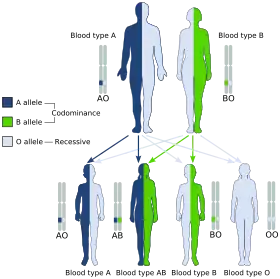

Blood groups are inherited from both parents. The ABO blood type is controlled by a single gene (the ABO gene) with three types of alleles inferred from classical genetics: i, IA, and IB. The I designation stands for isoagglutinogen, another term for antigen.[31] The gene encodes a glycosyltransferase—that is, an enzyme that modifies the carbohydrate content of the red blood cell antigens. The gene is located on the long arm of the ninth chromosome (9q34).[32]

The IA allele gives type A, IB gives type B, and i gives type O. As both IA and IB are dominant over i, only ii people have type O blood. Individuals with IAIA or IAi have type A blood, and individuals with IBIB or IBi have type B. IAIB people have both phenotypes, because A and B express a special dominance relationship: codominance, which means that type A and B parents can have an AB child. A couple with type A and type B can also have a type O child if they are both heterozygous (IBi and IAi). The cis-AB phenotype has a single enzyme that creates both A and B antigens. The resulting red blood cells do not usually express A or B antigen at the same level that would be expected on common group A1 or B red blood cells, which can help solve the problem of an apparently genetically impossible blood group.[33]